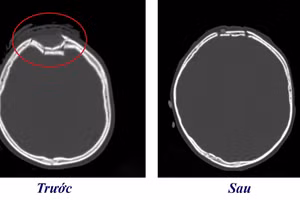

GD&TĐ - Bệnh viện Trung ương Quân đội 108 tiếp nhận nam sinh chấn thương sọ não do chìa khóa cắm sâu ở đầu, xuyên qua xương sọ vào nhu mô não khoảng 3 cm.